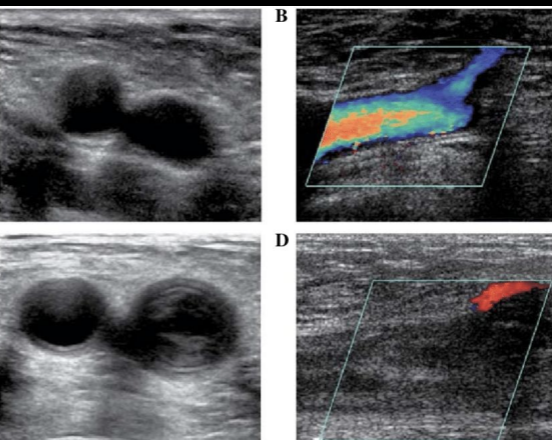

13

A

Varice en Doppler